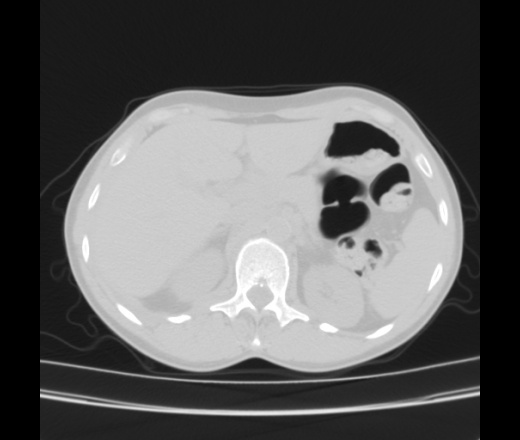

Женщина 55 лет. Жалобы на одышку, кушель с мокротой белого цвета, повышение температуры до 38, слабость, потливость, похудение. Больна в течение месяца. Лечилась в стационаре ЦРБ с пневмонией справа. Из выписки ОАК СОЭ-55, эр-лей-тромб - в норме. Мокрота на БК -. Анализ плевральной жидкости лейкоциты 12-13 , эритроциты измененые и неизмененые, клетки мезотелия.

За tbc c поражением внутригрудных л/узлов, правосторонним плевритом. Экс.перикардит. Признаки сердечной недостаточности.

Как второй вариант сочетание ЛГМ  и tbc, но тогда вопрос об имунном статусе.